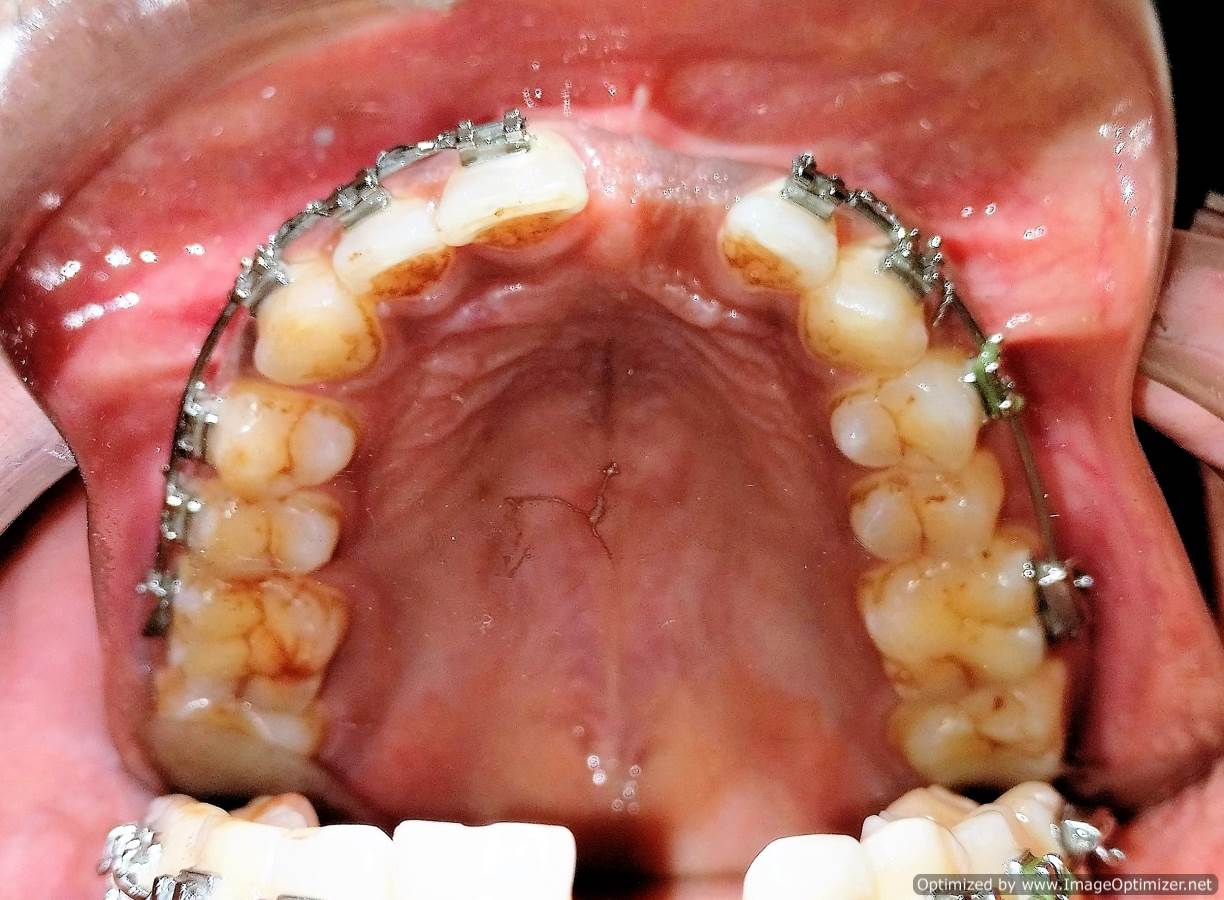

Dental Implant Case Report -03

Home / Case Report / Implant / Dental Implant Case Report -03